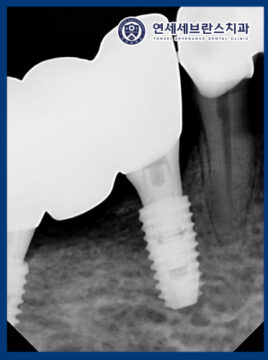

25.03.22

이후 아래쪽 부위에 대해서도

임플란트 식립을 진행하였습니다.

환자분께서는 당뇨로 인해

잇몸뼈가 상당히 소실된 상태였기 때문에,

임플란트 모의 식립을 통해

사전에 충분한 시뮬레이션을 진행한 후

가장 안정적인 위치를 선정하여

임플란트를 식립하였습니다.

이를 통해 잔존 뼈의 상태를 고려한

안정적이고 정밀한 치료가

이루어질 수 있도록 하였습니다.